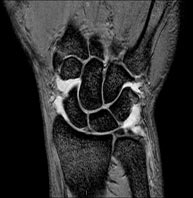

Exploració per a l'estudi de lesions en els tendons, els músculs i les articulacions. Molt útil per a la valoració de petites fractures inadvertides, lesions de lligaments i processos inflamatoris i degeneratius (artritis i artrosi). La durada aproximada és de 20 minuts. No utilitza radiació ionitzant. - RM de Mà / dits

Exploració per a l'estudi de lesions a tendons, lligaments i petites articulacions. És la prova que permet diagnosticar millor les capsulitis freqüents per traumatisme, l'artrosi i els trencaments de tendons. La durada aproximada és de 20 minuts. No utilitza radiació ionitzant. - RM de Malucs

Exploració per a l'estudi de les lesions en petites estructures anatòmiques de l'articulació que solen lesionar-se en pacients que pateixen luxació o inestabilitat crònica. L'estudi ve precedit per una injecció de contrast a l'interior de l'articulació, realitzada sota control de raigs X. La durada total dels dos procediments és de 50 minuts. - Artro-RM de Canell

Exploració per a l'estudi de les lesions en petites estructures anatòmiques de les seves articulacions com ara lligaments i cartílag. L'estudi ve precedit per una injecció de contrast a l'interior d'una de les articulacions, realitzada sota control de raigs X. La durada total dels dos procediments és de 50 minuts. - Artro-RM de Maluc

Exploració per a l'estudi de les lesions en petites estructures anatòmiques de l'articulació, com ara el cartílag i els meniscs, principalment els ja operats. L'estudi ve precedit per una injecció de contrast a l'interior de l'articulació, realitzada sota control de raigs X. La durada total dels dos procediments és de 50 minuts. - Artro-RM de Turmell